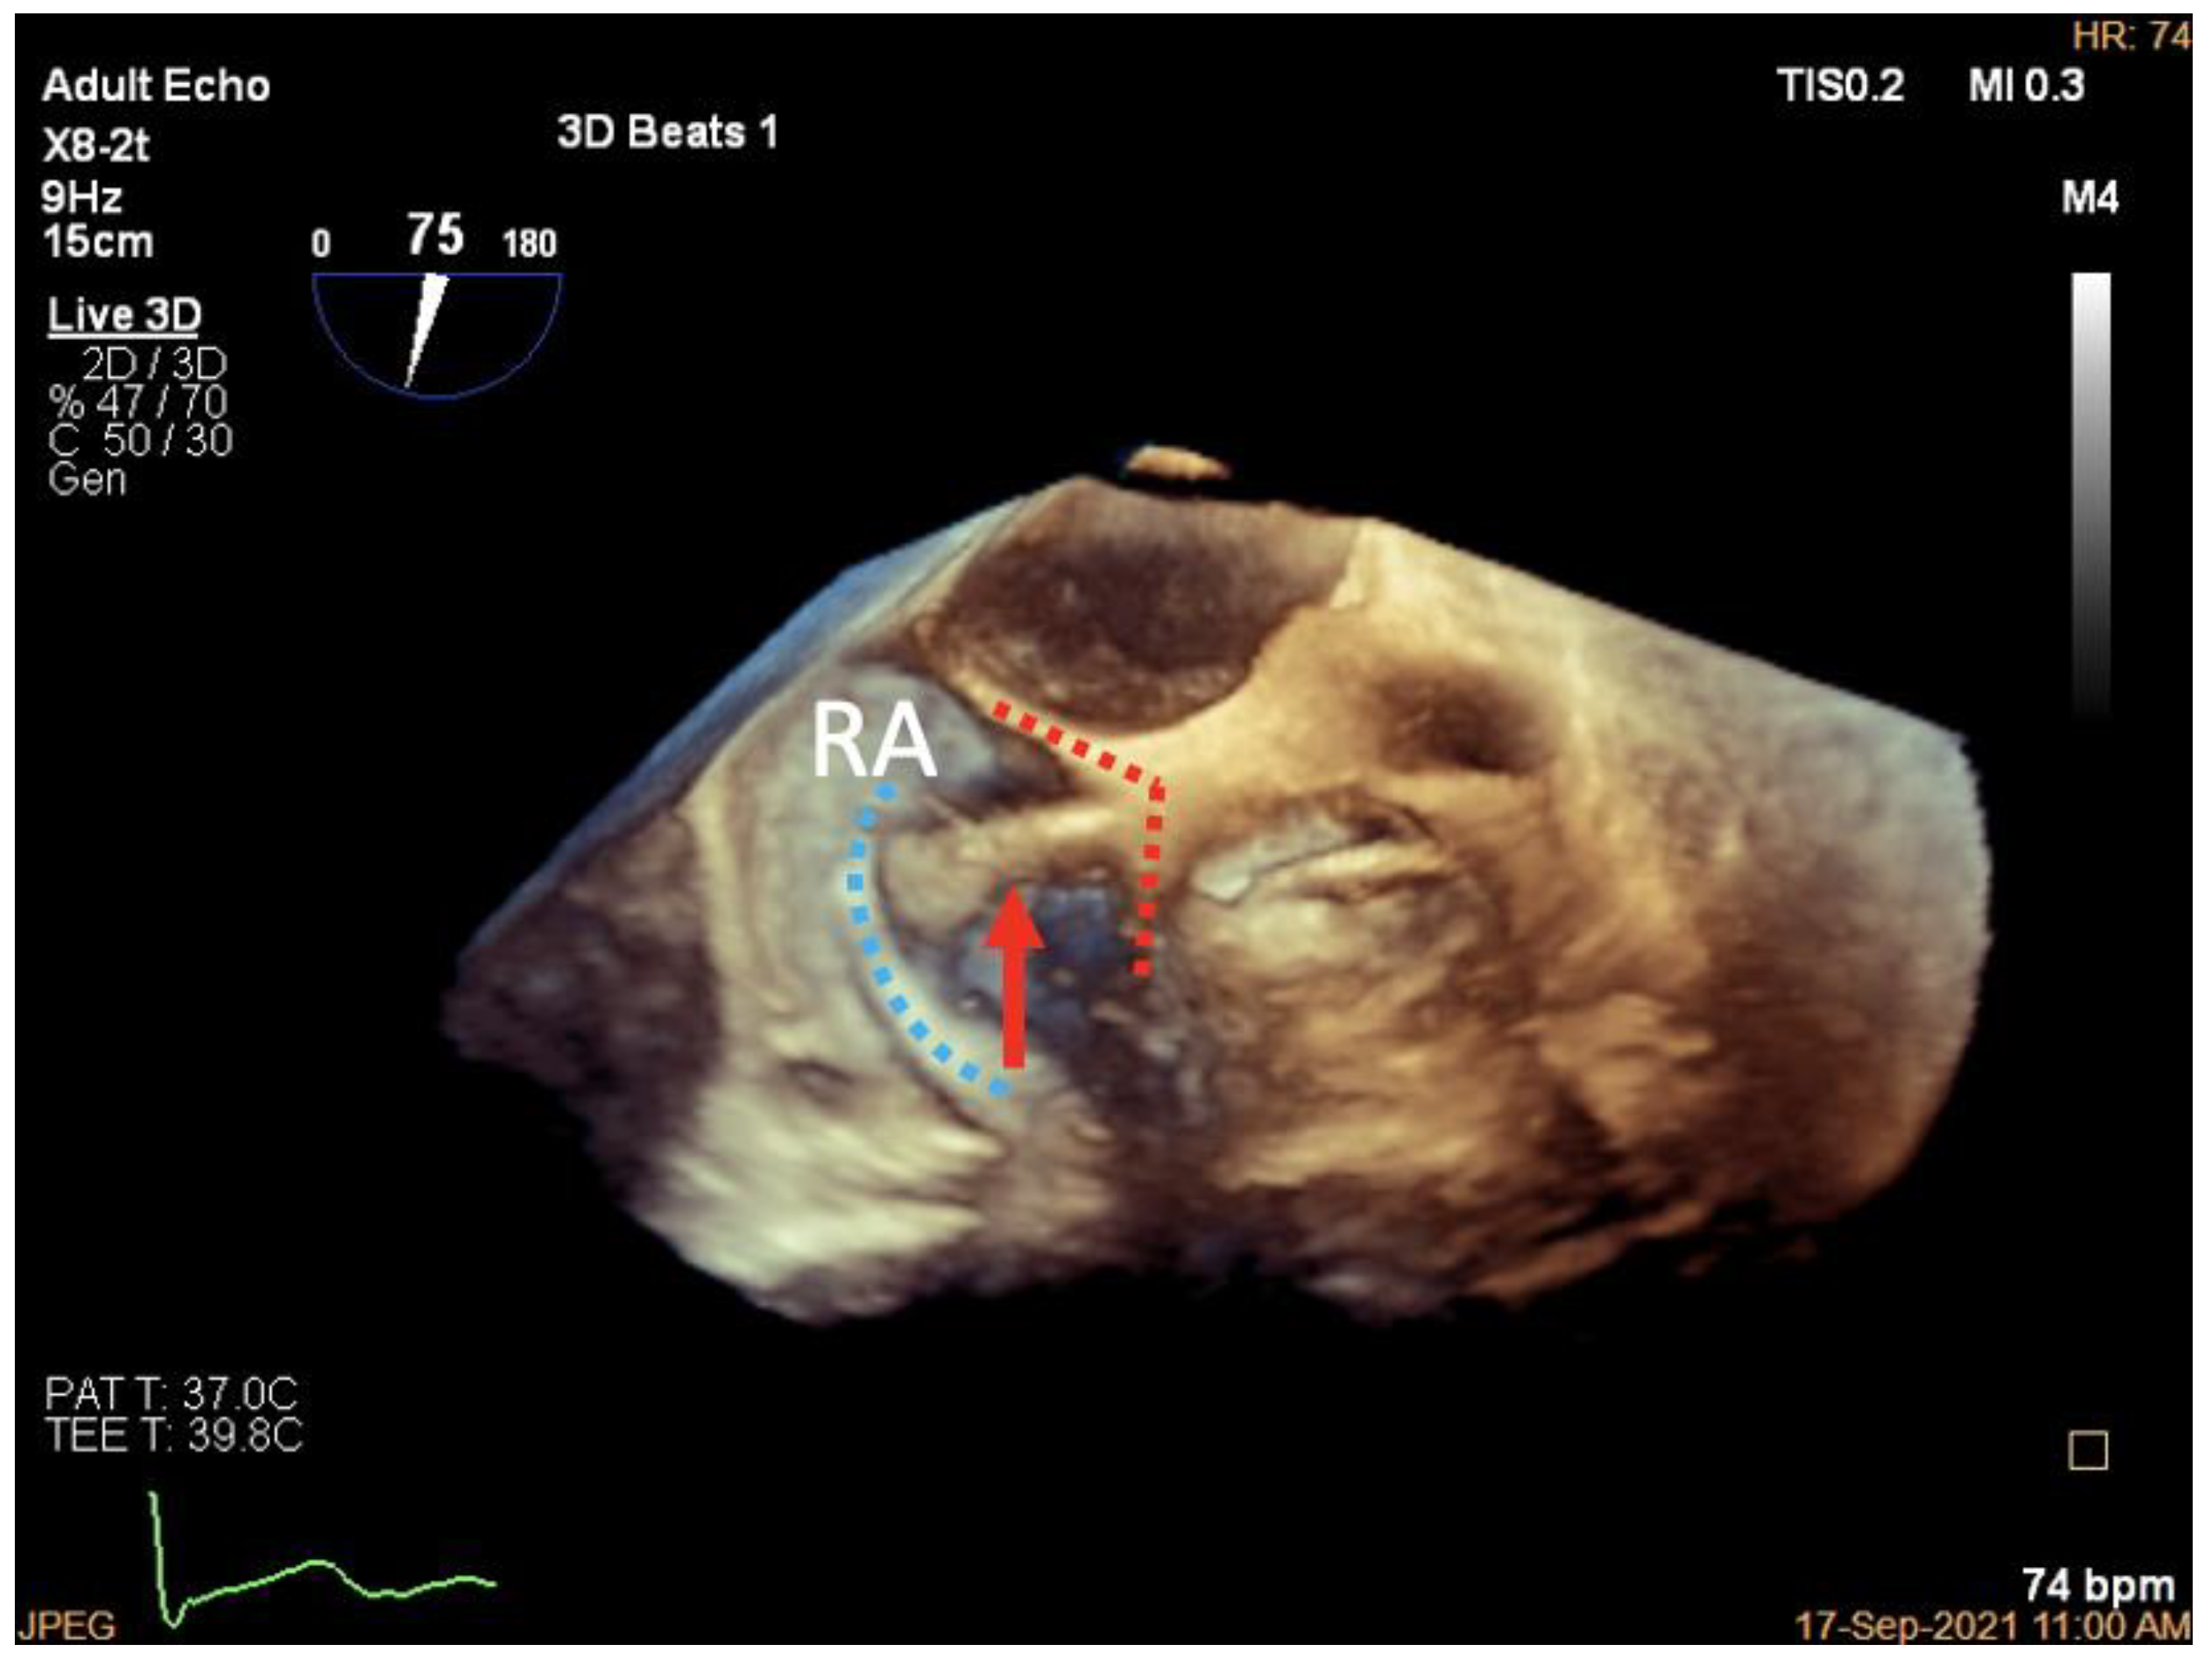

3.1. Patient Selection

3.5. Valve Function Assessment